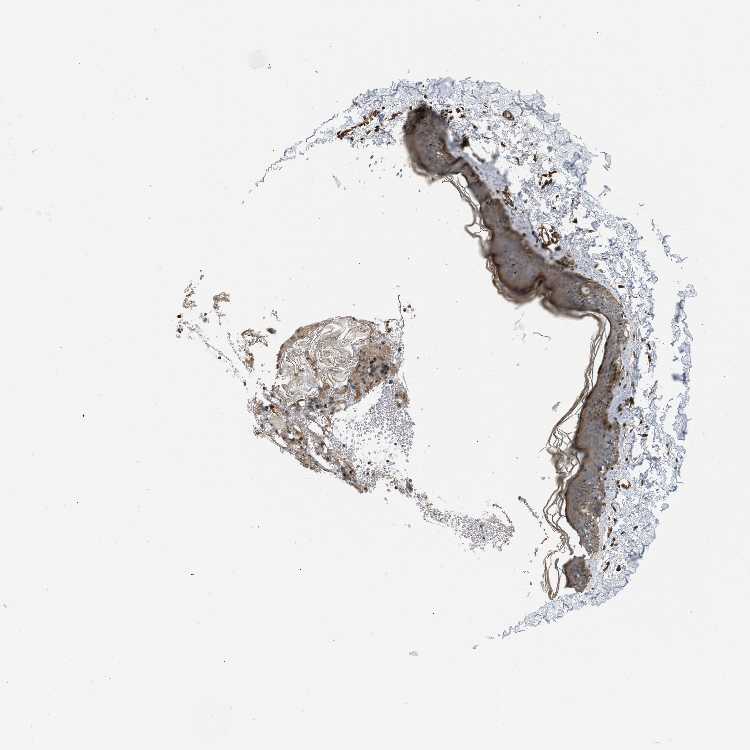

SKIN 1 - Antibody stainingi

Antibody staining in the annotated cell types in the current human tissue is reported as not detected, low, medium, or high, based on conventional immunohistochemistry profiling in selected tissues. This score is based on the combination of the staining intensity and fraction of stained cells.

Each image is clickable and will lead to virtual microscopy that enables deeper exploration of all samples and also displays staining intensity scores, fraction scores and subcellular localization as well as patient and tissue information for each sample.

Antibody HPA008399Antibody HPA017017Antibody CAB015221

Langerhans LowMediumLow

Fibroblasts LowNot detectedMedium

Keratinocytes MediumMediumLow

Melanocytes MediumNot detectedLow